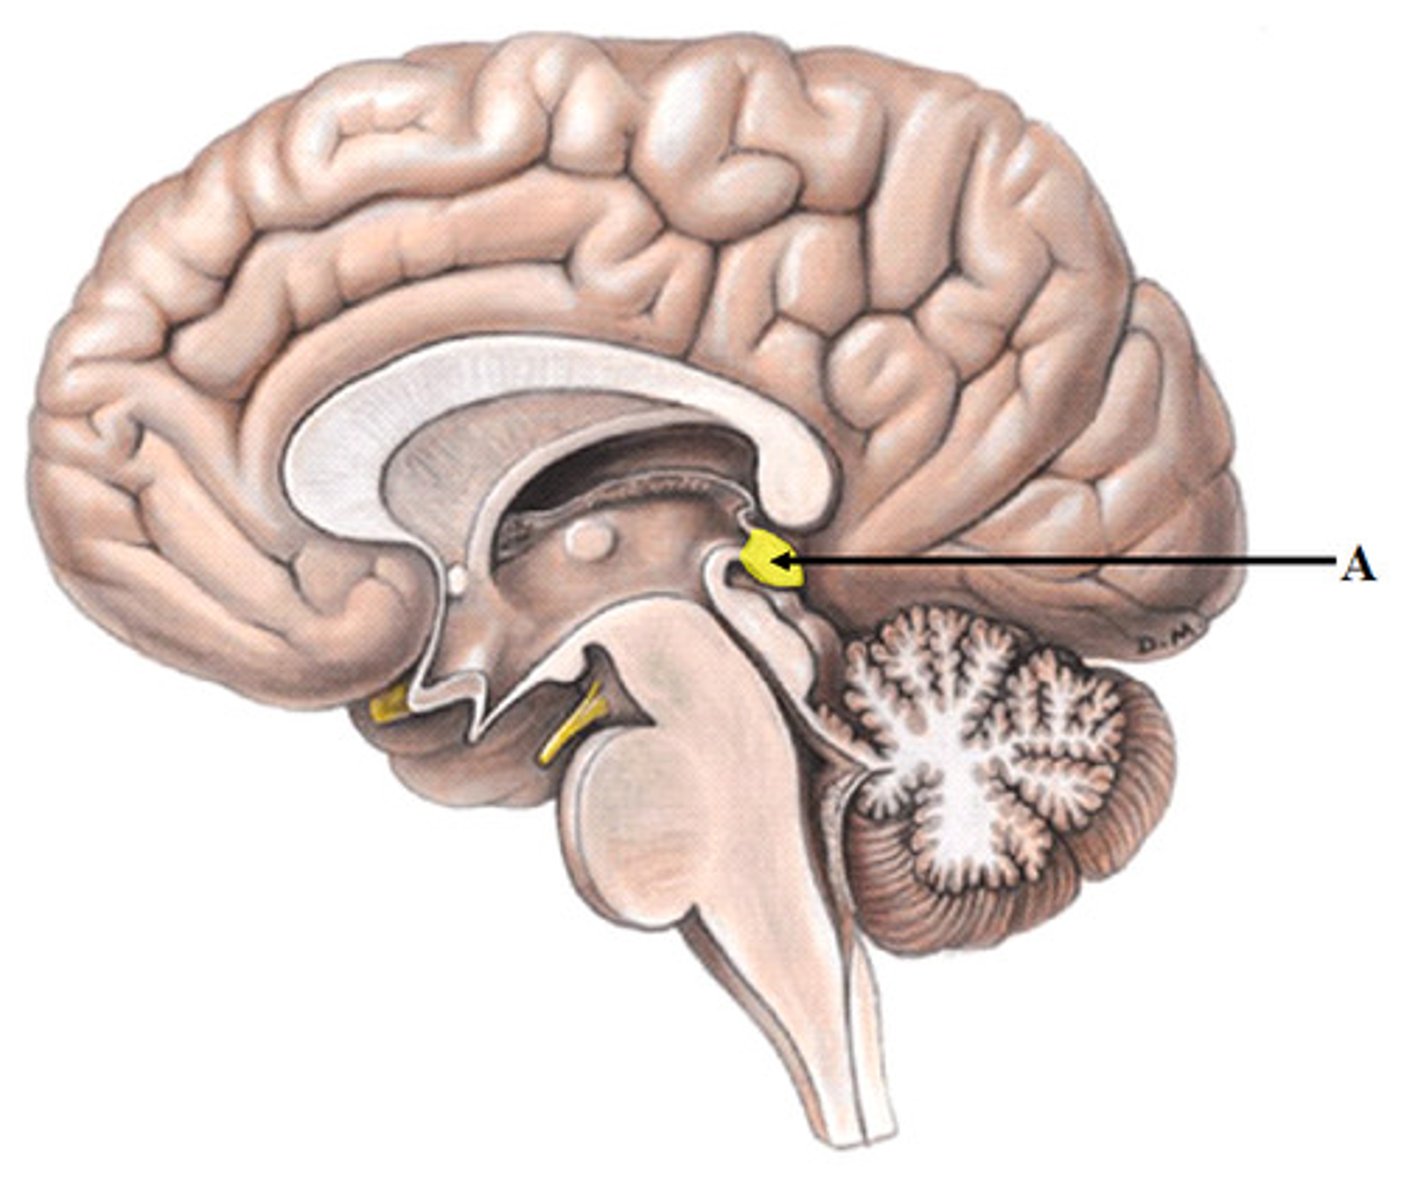

pituitary gland

gland at the base of the brain that dangles under the hypothalamus

pituitary gland hormones

LH, FSH, GH, TSH, ACTH, Prolactin, Oxytocin, ADH